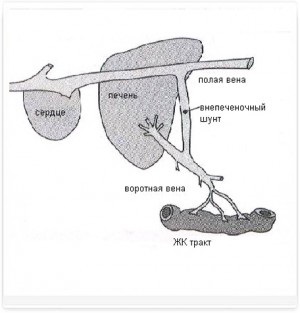

Porto (portocav) șunturi - este conexiuni vasculare anormale între vena portal hepatic (vas de sânge care se conectează tractul gastrointestinal la nivelul ficatului) și circulația sistemică (Figura 2, 2a).

Schema Fig.1 a fluxului sanguin normal de portal

Figura 2 și 2a. Schemele fluxului sanguin portal patologic